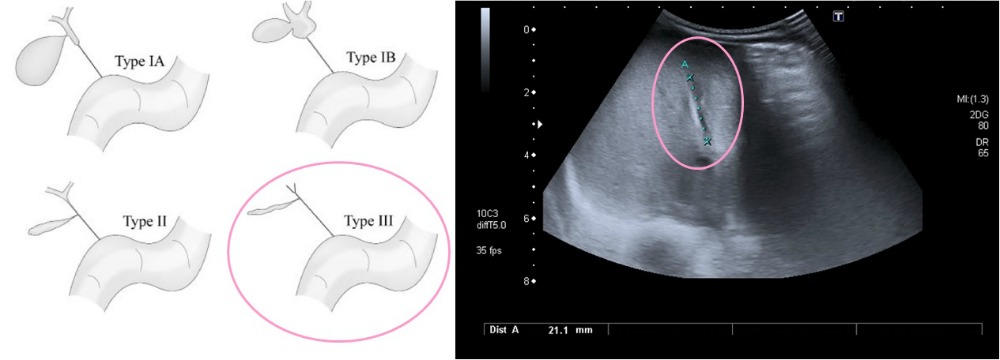

¿Qué prueba complementaria es fundamental para establecer el diagnóstico de coléstasis?